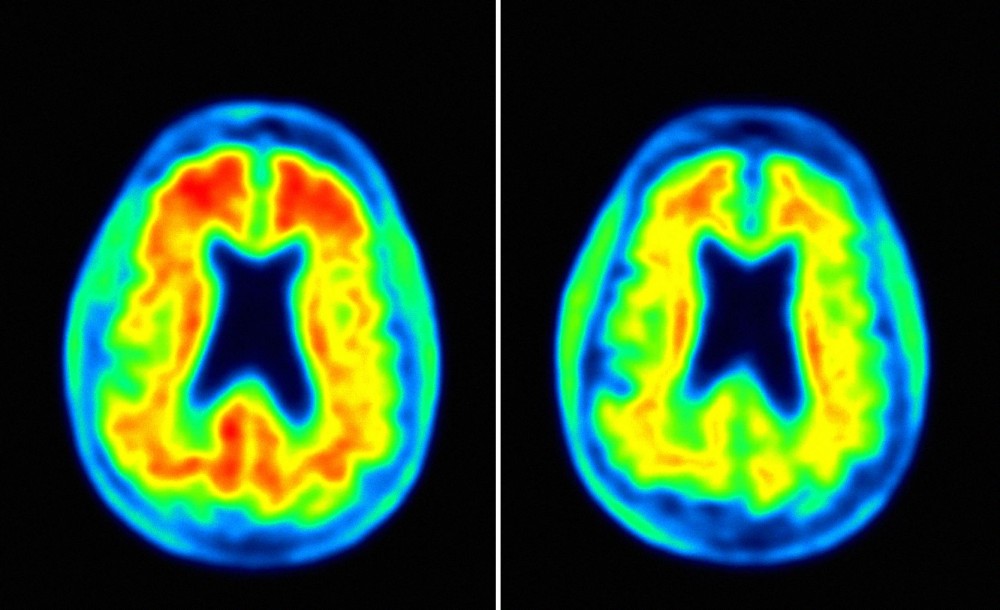

En los primeros ensayos un anticuerpo experimental ha conseguido eliminar las placas que se acumulan en el cerebro antes de que aparezca dicha enfermedad. Aducanumab es un fármaco experimental presentado […]